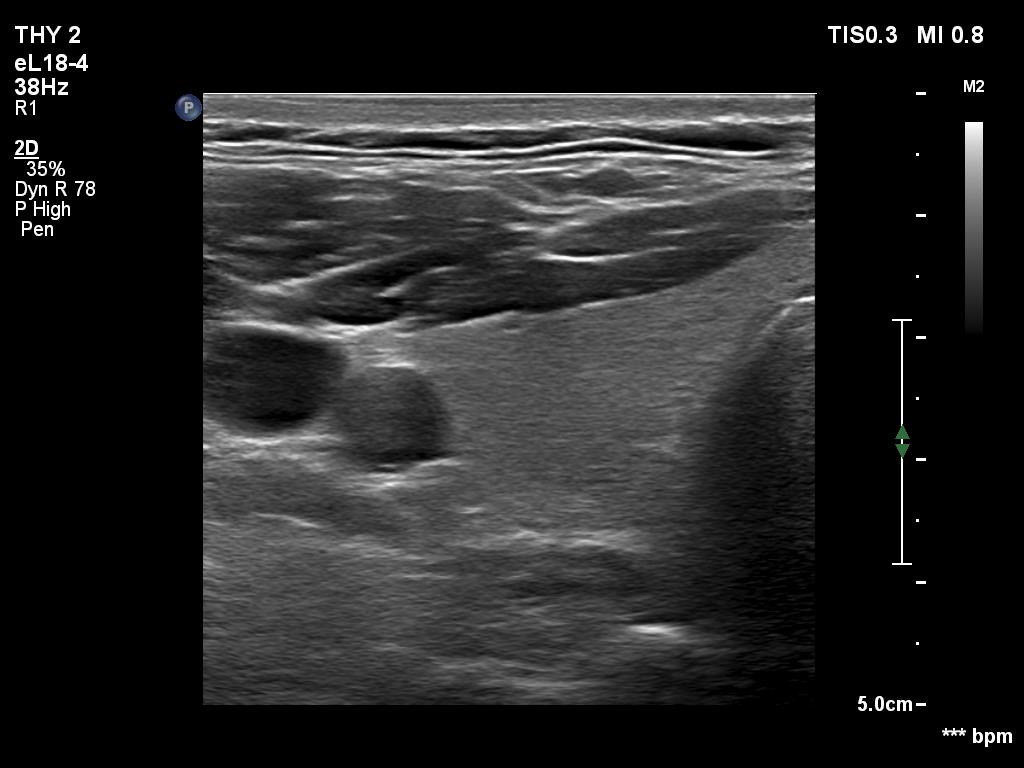

Ultrasonography. The thyroid was echonormal and had two cystic lesions in the left lobe. With higher frequency, the dorsal part of both lobes presented with hypoechoic blurred areas. With frequency decreased, these areas have disappeared.

Comment. This case illustrated the well-known inverse relation between penetrance and resolution. Better the former worst the latter and conversely. This has particular and practical importance if we examine obese patients using high-end equipment with high frequency. In such patients the obesity can significantly worsen the penetrance. This can be solved by decreasing the frequency and remove all software harmonization.